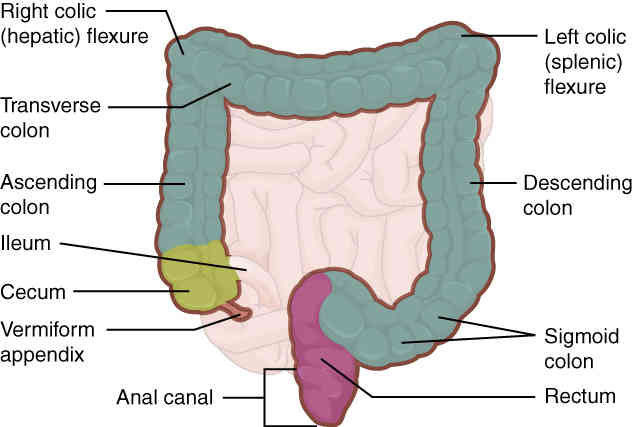

This page is under construction. For now, it is just a resource of the images found in the OpenStax Anatomy and Physiology Handbook. It wil slowly change into a revision tool. Each slide has a number. Use this to refer to the slide. When completed, it will have an unlabelled section, with labelled slides in parallel. On the unlabelled slides, write your answer and use the labelled slide to assess yourself. Keep track by also noting the number on each slide. Improvement at each attempt is important, more so than full marks on a first attempt.